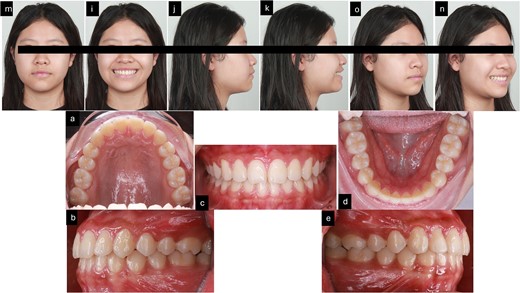

After 16 months of orthodontic treatment, all treatment objectives were successfully accomplished. This resulted in a well-aligned dentition with all spaces closed, leading to enhanced facial aesthetics, and retracted upper incisors. The overbite and overjet were within normal ranges, achieving a Class I occlusion. There was also a visibly reduced GS after treatment. The superimposition and cephalometric analysis table before and after treatment showed significant improvements in profile and incisor inclination, the clear aligner removable appliance was used for retention (Figs 5 and 6, and Table 1). After 2 weeks of periodontal surgery, the patient’s gingival line has healed exceptionally well. It now wraps around the tooth roots in a scalloped shape, with no black triangles or exposed tooth roots. The surgery also fixed the patient’s GS, resulting in an ideal gingival exposure. As a result, the crowns of the teeth are more visible and stable up to 3 months (Fig. 7).

3 months follow-up after treatment. (m–n) Extra oral pictures; (a–e) intraoral pictures.